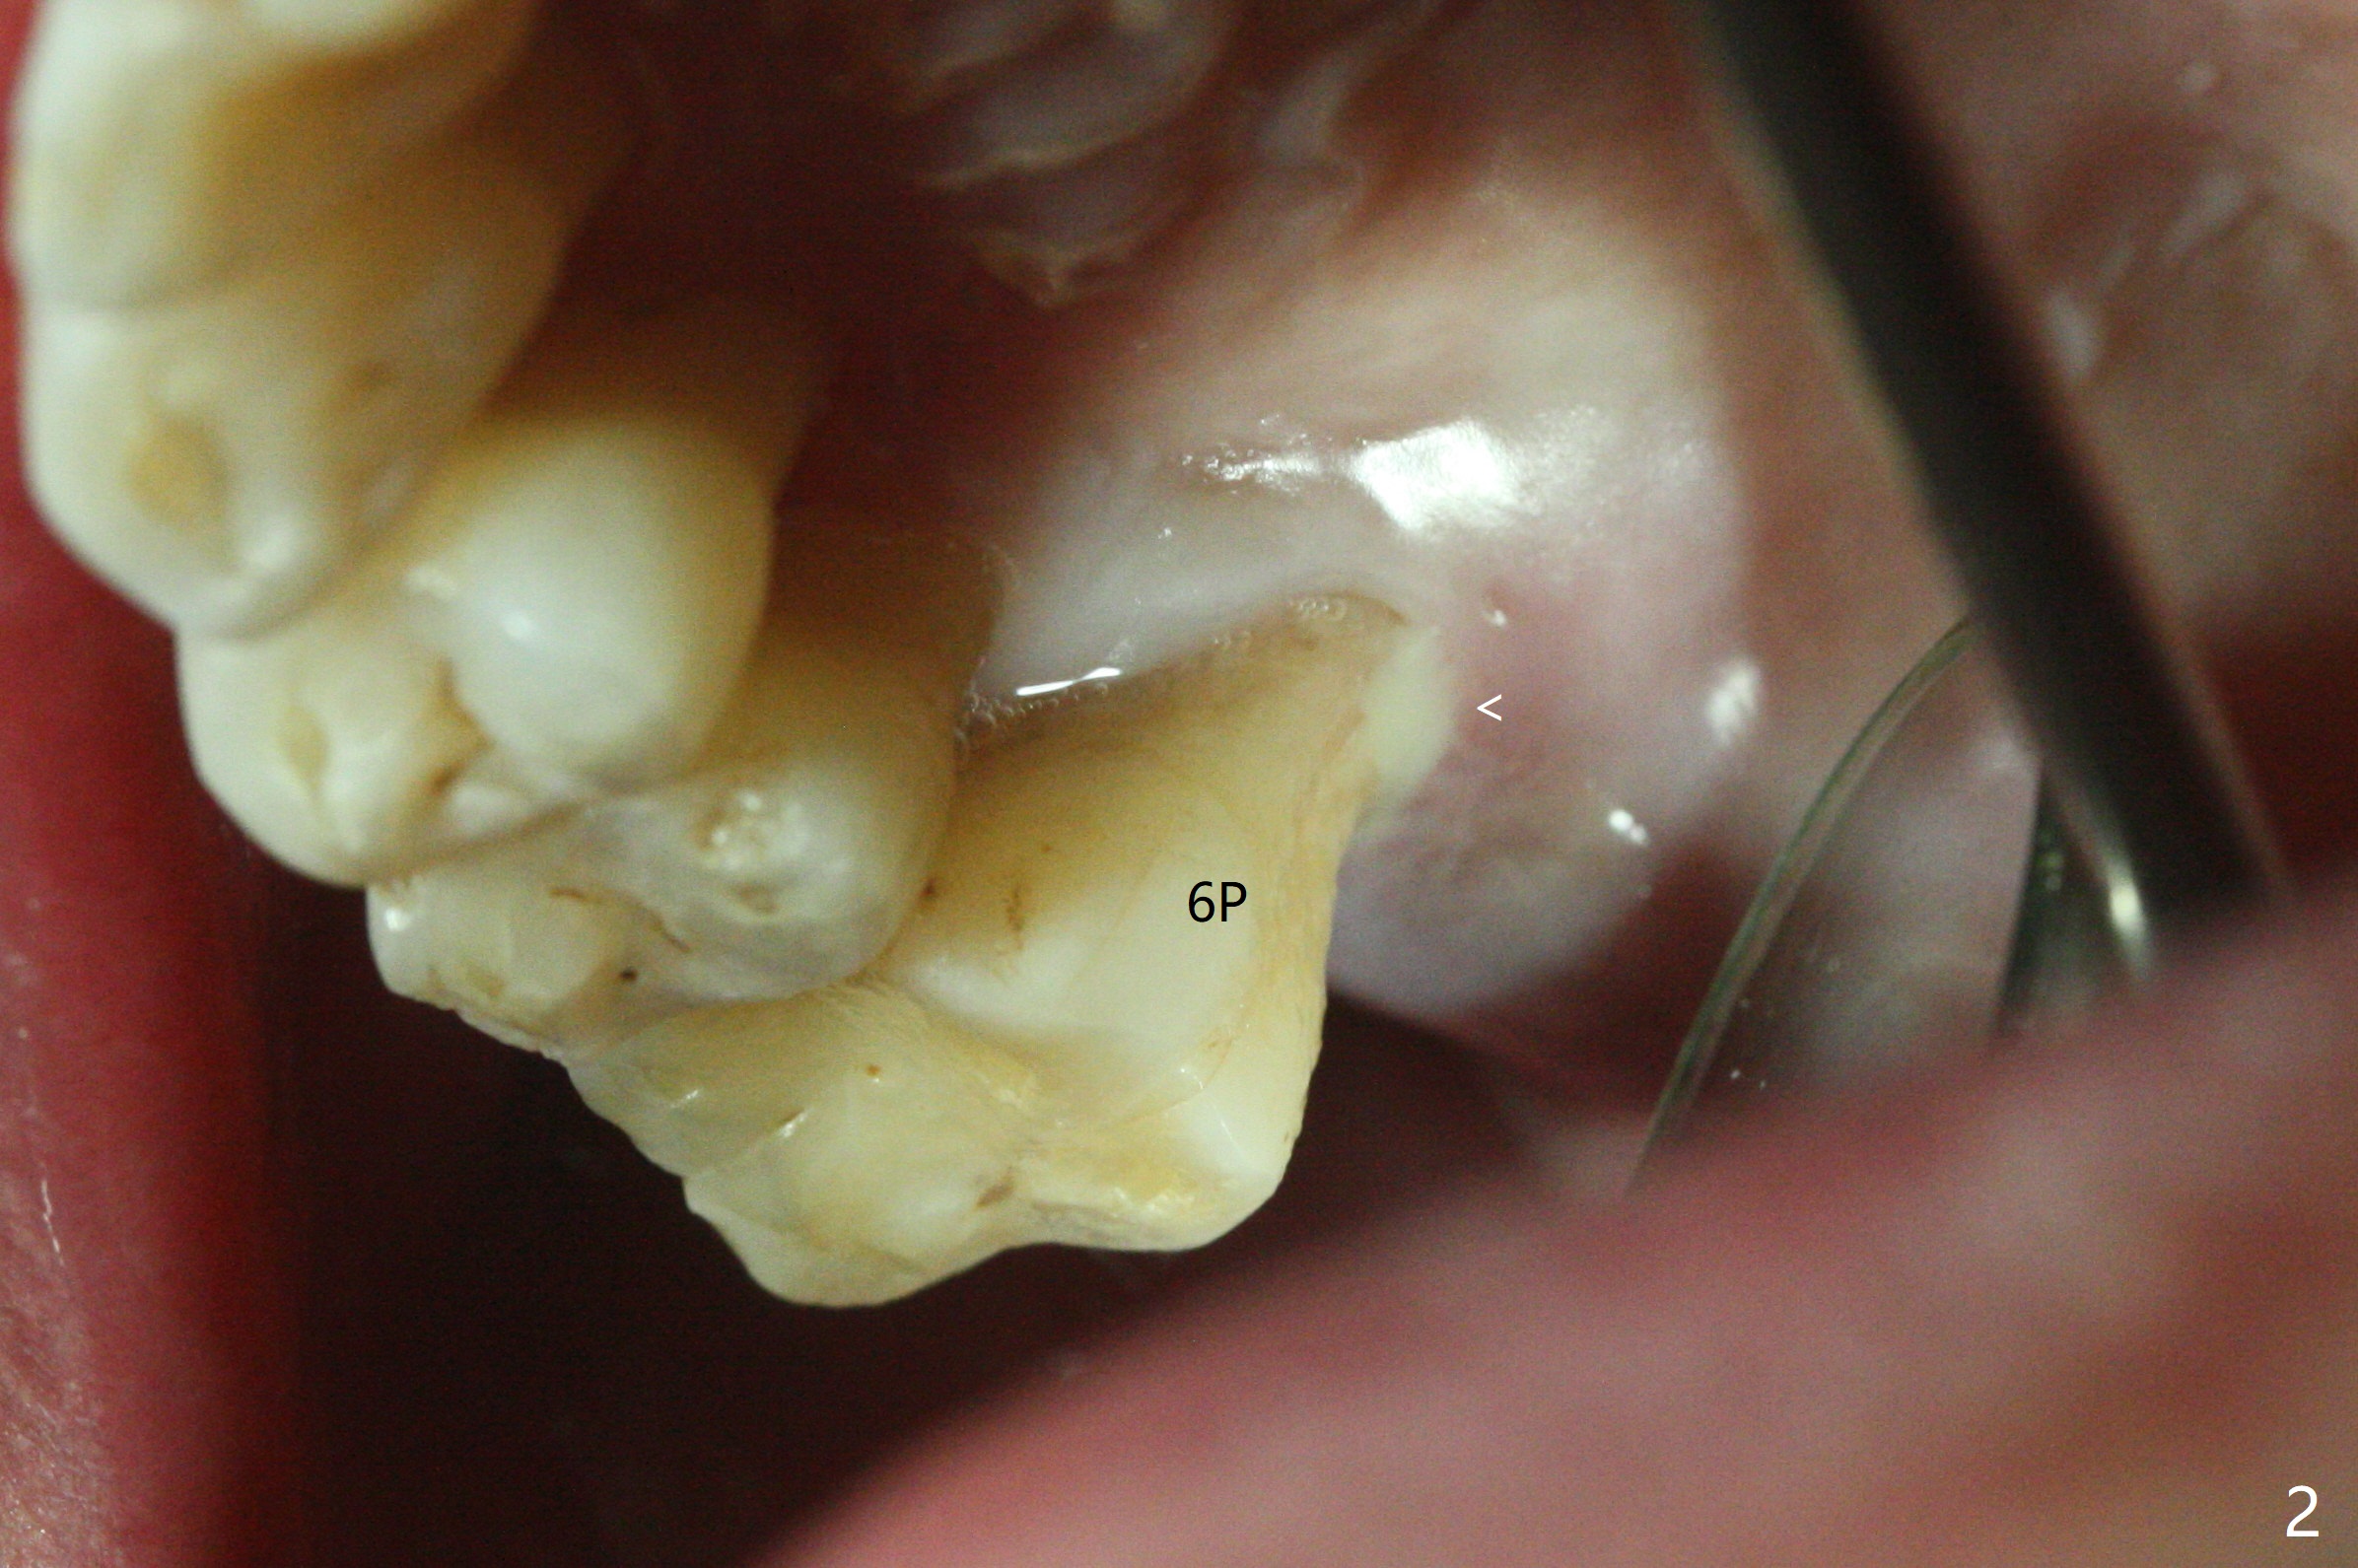

69岁男2.5年前CT显示右上7根尖骨质很薄(图一:*),大约一年后拔除,没植骨。上周拔除8时,发现6腭侧牙周袋出脓(图二:<)。拔除后者清创后,往远中牙龈下分离7位点,然后6,7植骨(图三:*),7骨质高度增加一倍(植骨后近7毫米)。覆盖两片PRF膜,近中放置小块胶原塞(牙槽嵴高),4-0 PGA缝合,置放间隙保持器(放置攀(loop),增加固位)和牙周敷料。术后13天敷料保持原位,卫生也好(图四),病人明天到外地几个月,交代他两周后撤除敷料。没有不便,不必去掉保持器。